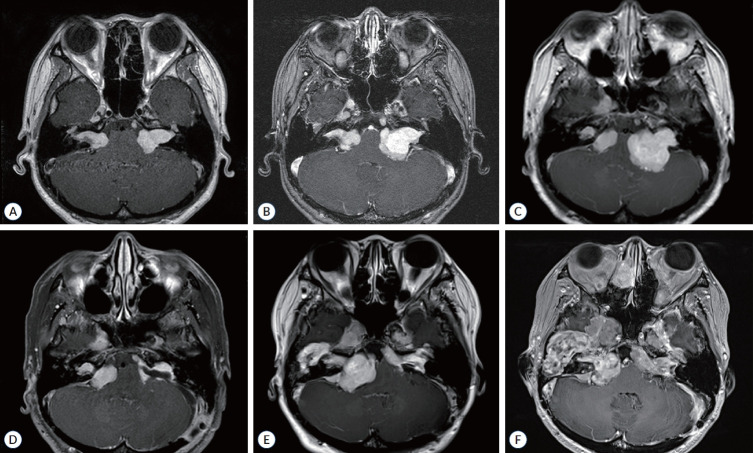

Abstract Image